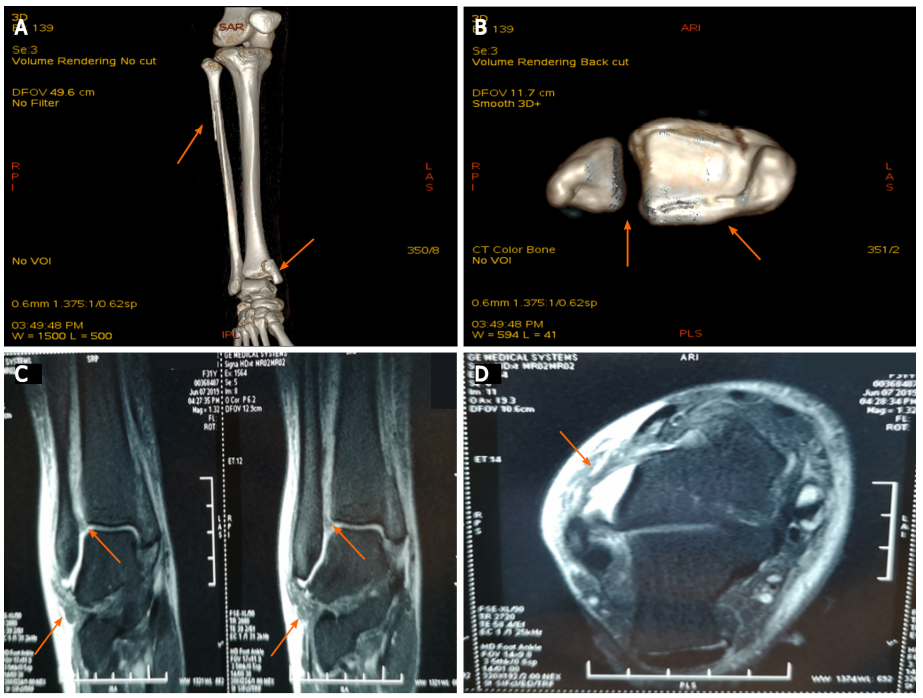

图2:A:踝关节和小腿的CT正面图(箭头);B:踝关节CT扫描(箭头);C:踝关节的矢状位MRI(箭头);D:踝关节的横断面MRI(箭头);A和B:CT显示腓骨近端骨折、下胫腓关节分离、内踝骨折累及后踝(箭头);C和D:MRI显示胫腓前下韧带和距腓前韧带断裂(箭头)。